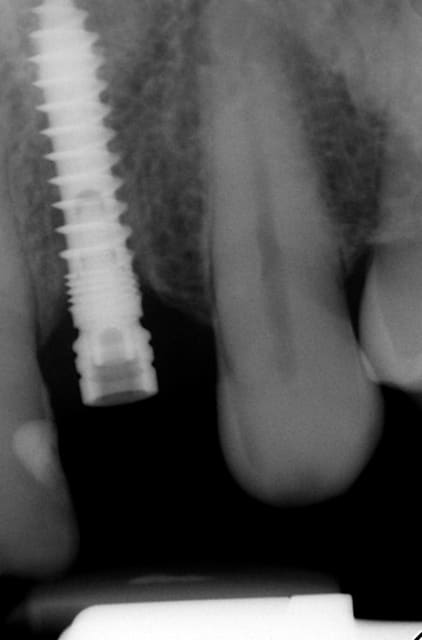

Merci pour tes questions. Si tu as une gencive "normale" (2-3 mm) ( avec le foret on peut savoir grâce aux mesures ) tu arrêtes à implanter si le truc en métal (je ne sais pas en francais en allemand Einbringhilfe) arrive à la gencive. Si la gencive fait plus de 3mm tu pousses un peu plus (le début de la fenêtre du Einbringhilfe est à un millimètre , la fin de la fenêtre = 3mm ) ...on vérifie avec une petite radio (pas OPG) .

En dessous il y a des photos, dans une on voit (troisième) qu il n y a pas de resorption de l´os après 14 ans, ce que l´on voit c´est l´os très fin condensé sur l´implant.

Le premier photo c´est une erreur parce que le périoste est blessé et les foret "trop" grands.